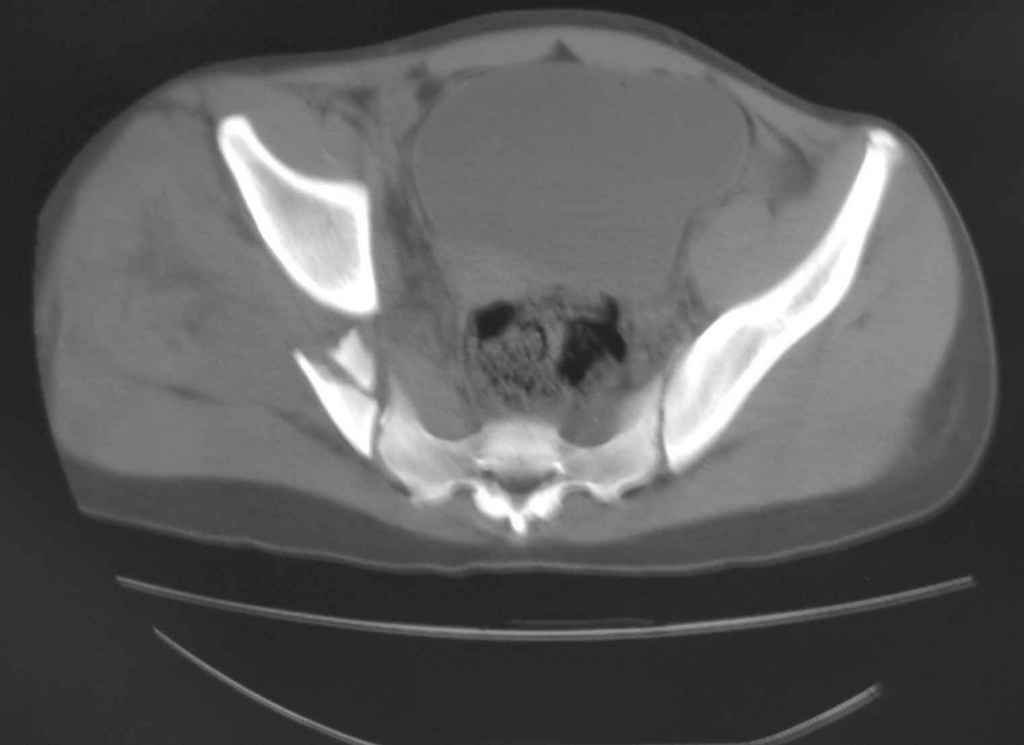

Принципиально важно видеть все срезы КТ через вертлугу, так как тактика лечения будет в первую очередь обусловлена характером перелома ветрлужной впадины, во вторую - вертикальным смещением таза ( где варианты - от банального скелетного вытяжения до ВЧКО или накостного остеосинтеза - в основном зависит от пресловутой "позиции кафедры")

Уважаемый Алексей, на представленных Вами снимках имеется вертикально-нестабильное повреждение тазового кольца без повреждения вертлужной впадины. Учитывая это, а так же растущий возраст ребенка я бы выбрал аппарат внешней фиксации в виде кольцевой опоры, т.к. не смотря на оскольчатый перелом крыла в переднем отделе можно ввести минимум 2 стержня + 1-2 надвертлужно. Этого будет достаточно чтобы "зацепится", выполнить репозицию и дальнейшую фиксацию. Перелом шейки по моему лучше прооперировать 3 канюлированными винтами по АО.